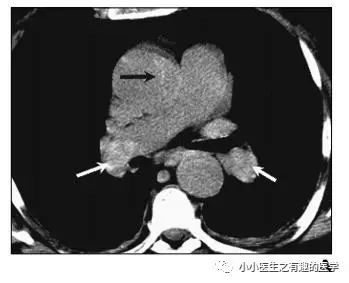

不光是肺栓塞,连主动脉夹层,都发现了。

牛。我来标记一下。

究竟是美国的设备好,还是他们认真仔细?两者相辅相成。生产工具很重要,人的努力也很重要。